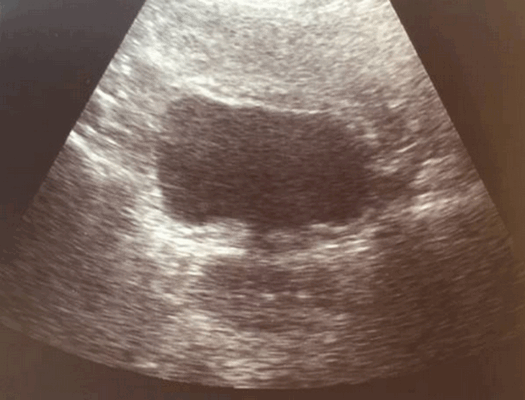

УЗИ признаки калькулезного холецистита.

Утолщение стенки желчного пузыря — это частая диагностическая находка. Утолщением является размер стенки более 3 мм. При УЗИ утолщенная стенка имеет слоистый внешний вид, а на КТ выявляется гиподенсный слой, что соответствует субсерозному отеку.

Слева — УЗИ — желчного пузыря у 59 летней женщины с острым холециститом. Субсерозный отек так, как гипоэхогенное утолщение между гиперэхогенными слоями (мышечным и слизистым). Справа — КТ брюшной полости с контрастным усилением. Также визуализируется субсерозный отек так, как наружный слой гиподенсный.